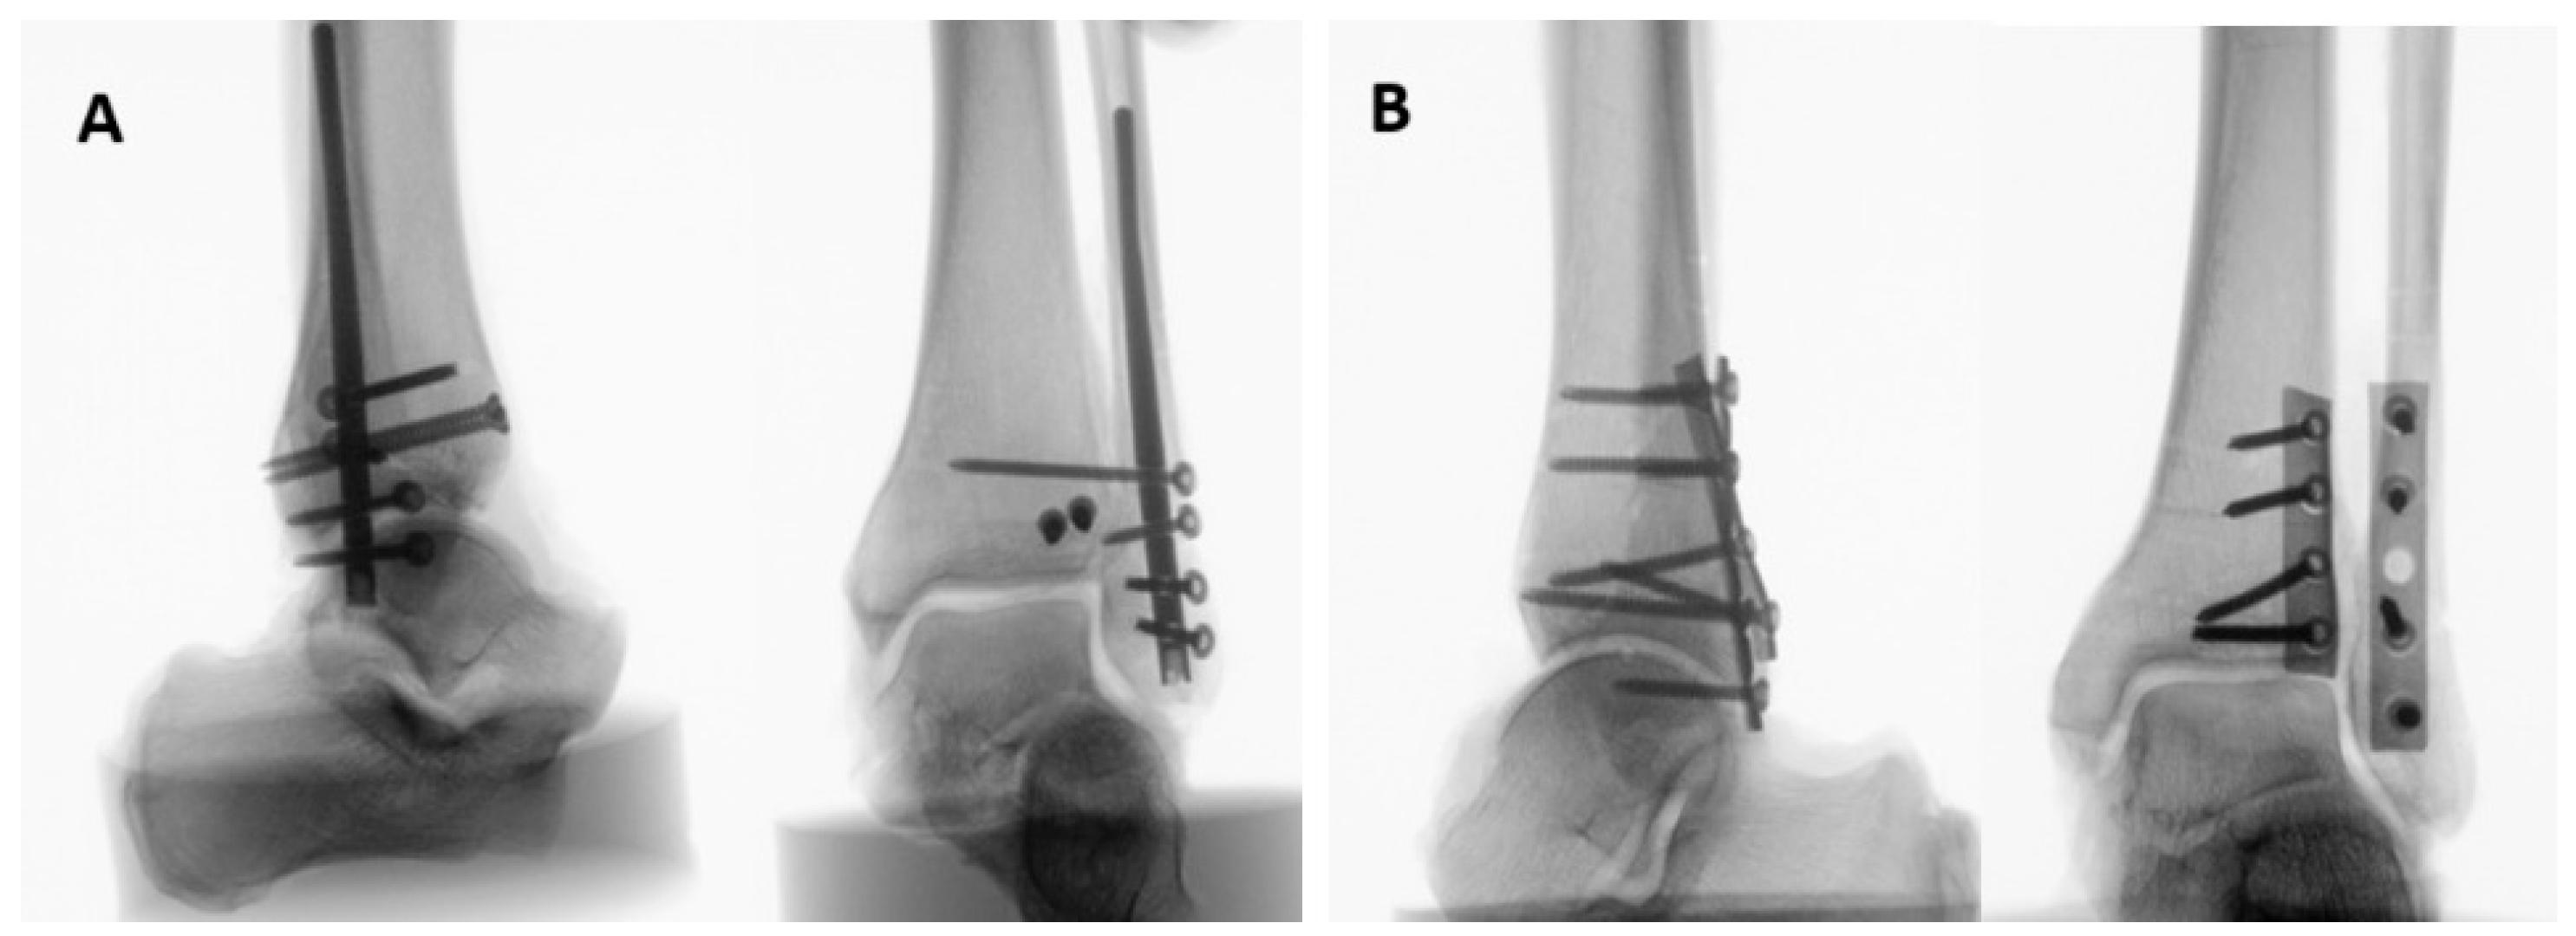

2. Materials and Methods